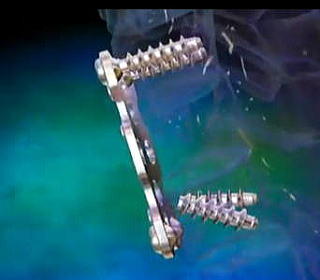

手術では、切開後、下の図にあるような第二頸椎を取り巻く筋肉や脊椎、末梢神経、動静脈などどへの損傷、影響を最低限に腰から採った骨を第一頸椎と第二頸椎の間に挟みつつ、4本のチタンスクリューと2本のチタンロッドで幹部を固定する。スクリューをうつ場所はドリルで穴を開けるという。 ◆手術の内容とInformed Consent 入院して一週間後、私は大手術を受けることになる。 手術の内容だが、折れて陥没した第二頸椎を自分の腰からとった骨を挟んで第一頸椎にチタン合金で構造化し固定化するもので、チタンのスクリューやロッドを6本使っている。まだ3次元画像はもらっていないが、後に術後のレントゲン写真を見せられた。これについても入手次第、掲載したい。 下は手術前夜に執刀医が私と妻との間で行われた Informed Choice and Consent時に示した手術の物理的な概念図である。構造設計図といってもよい。これは個室の前にあるカンファレンス室で執刀医、青山、妻の3人で1時間ほどかけ行われた。

そして翌日の11月19日午後から夜に及ぶ手術では、妻が個室(病室)に待機し、万一インフォームドコンセントの内容からはずれて麻酔、手術などをする場合、すぐに執刀医から妻に連絡が行くとされた。 手術では、当初通りに行われたこともあり、待機する妻への連絡は終了時までなかった。 ◆手術の具体的内容 C1が第一頸椎、C2が第二頸椎であり、上の図が側面図、下の図が組の後ろから見た側面図である。スクリュー4本、ロッド2本は素材がチタン合金であい、櫓を組んで第一、第二頸椎を腰から取った自分の骨を挟んで固定する。  主治医がInformed Consentで示した青山貞一手術の概念図(1) 慈恵医科大付属病院脳神経外科 2010.11.18 下は青山が上図を元にのちに作成したもの。ただし、下図は第二頸椎骨折、陥没後ではなく、健康な頸椎上にチタンのスクリューやロッドを書き加えている。さらに3次元で立体的に可視化しないとその構造は理解されにくい。  青山貞一による手術の概念図 下は使用するチタンスクリューのイメージである。   出典:http://www.sophiatech.co.jp/implans/screw_image/screw_image.html 手術ではたとえば以下のようにして使うことになる。ただし、以下はイメージ図。   それぞれの位置 背面図 出典:http://www.orihime.ne.jp/~one-/tekious.htm 手術の前々日、前日と2回に渡り麻酔専門医から何度も説明を受けた。麻酔の手順、心得などについても説明を受けた。 大手術は慈恵医科大学付属病院の脳神経外科、麻酔科などの専門医師5名による特別グループ構成で11月19日午後から夜にかけ行われた。 12時過ぎ、中央棟16階にある私の個室から看護師により車椅子で16階からエレベータを使って3階の手術に向かった。手術室到着後、麻酔専門医により点滴形式で全身麻酔が行われた。覚えているのはここまでである。 その後7-8時間はまったく記憶はなく夢も見ていない。 手術後すぐに、5階にある集中治療室(ICU)に移された。 ICUでは主動脈(Aライン)、静脈、末梢系はじめ各所に10本以上のチューブが体に差し込まれており、またオシッコなどの排出系もすべてチューブとなっていて身動きできなかった。入院後、一番きつかったのはこのときである。 慈恵医大病院中央棟のICUはかなりの数あり、手術を受ける患者には希望すると手術の前日までにICUを見学することができる。私は希望し前日にしっかり見学しICU側から説明も受けた。 肝腎な手術の内容は、上述のように落下転倒で折れ陥没した第二頸椎と第一頸椎の間に、腰から取った骨を挟み約2mm直径のチタン(金属)2本とそれにブリッジをかけるように固定することでした。チタンの棒は計4本使用している。 上記の手術内容についても、外来検査時から手術の前日まで、あらかじめ模型とグラフィックスをもとに主治医に何度も説明をしてもらった。 手術内容と方法には、当然のこととして代替案が多数ある。そのかかから医師と議論しながらひとつを選ぶことになった。代替案によりプラス、マイナス、リスク、費用が変わる。 また、もし手術で実際に首を開いたところ、第一案が難しい場合は第二案、第三案と次善の策についても優先順位を付けることになった。この説明と質疑にはかなりの時間が費やされた。この辺はInformed Consentの主要部分となる。 本来、第一頸椎と第二頸椎はそれぞれ独立して動くことで、人間は誰でも首が自由に回るのだが、第一と第二を固定化したので、手術によって直っても仰角、回転角ともに制限がある。リハビリなどにより健康な方の70%程度まで戻るかも知れないと言われた。 上述のように、私自身、3週間に及ぶ入院の中では、ICUから個室に移った20日が一番きつかった。翌日は一日安静にしていた。実のところ私が入院中に安静にしていたのは、この日(20日)くらいかも知れない。 19日夜から点滴が開始されていたが、20日の夕方から食事がだされた。食事と並行してブドウ糖などの点滴を行い栄養を体に送り込んだ。点滴にはブドウ糖とともに手術時の各種傷口に対応するための抗生剤が含まれる。 22日以降、手術に関連した痛みがかなり減ってきた。術後、一切の鎮痛剤を使っておらず看護師さんらはびっくりしている。痛みは人によって個人差があるようだ! ところで今回は、11日に東京都品川区にある旗の台脳神経外科に診察にでかけたときから、現在に至るまで徹底的にInformed choice and consentを心がけ、すべてに渡り主治医(脳神経外科執刀医、呼吸器主任、糖尿など生活習慣病関連の主任、麻酔主任)らからの説明を受け、その都度理解、認識した上で判断した。 たとえば呼吸機能を回復させようとすると血糖値やLDLが上昇するなど新たな問題が起こるが、それらを承知の上で何を優先するかが術前の大きなポイントとなる。これについても、私のここ数年の経験を伝えた。 医者側も驚いていたが、やはり患者や家族は医者任せ、看護師まかせではなく、主体性を持って対応することの大切さを実感している。 下は健康な人の第一頸椎(上)と第二頸椎(下)の側面図である。 第一頸椎 出典:http://video.about.com/backandneck/Cervical-Spine-Anatomy.htm 第二頸椎 出典:http://video.about.com/backandneck/Cervical-Spine-Anatomy.htm 下のレントゲン写真は術後に撮影したものである。 退院後初の検査時に主治医より提供を受けた。第一頸椎と第二頸椎の間に腰骨を挟み、チタン合金で第一頸椎(長いスクリュー)、第二頸椎(短いスクリュー)で固定している様子が3次元の立体図で良く分かる。  手術後の頸椎レントゲン写真(2010/12/13) 出典:東京慈恵会医科大学付属病院脳神経外科 以下は、CT及びMRIで見た手術個所の断層図である。退院時、希望していたCT及びMRI断層画像データをCD媒体で提供された。画像は専用ソフトだけでなくWindowsXP,7などのブラウザでも見れる。  出典:東京慈恵会医科大学付属病院脳神経外科 下はCT画像に見る第二頸椎に入れたチタンスクリュー(ネジ)。断層撮影なので部部しか見れない。  CT断層画像に見る青山貞一の手術後(2010年11月20日撮影)。 慈恵医大付属病院 下もCT画像に見る第二頸椎に入れたチタンスクリュー(ネジ)。断層撮影なので部部しか見れない。チタンスクリューは4本、チタンロッド(棒)は2本入れてある。  CT断層画像に見る青山貞一の手術後(2010年11月20日撮影)。 出典:慈恵医大付属病院脳神経外科  CT断層画像に見る青山貞一の手術後(2010年11月20日撮影)。 出典:慈恵医大付属病院脳神経外科  CT断層画像に見る青山貞一の手術後(2010年11月20日撮影)。 出典:慈恵医大付属病院脳神経外科  CT断層画像に見る青山貞一の手術後(2010年11月20日撮影)。 出典:慈恵医大付属病院脳神経外科  CT断層画像に見る青山貞一の手術後(2010年11月20日撮影)。 出典:慈恵医大付属病院脳神経外科 下は腰の骨の採取場所を示している。また手術時の切開位置を示している。首の裏を縦に12cmほど切開している。  主治医ががInformed Consentで示した青山貞一手術の概要図(2) 慈恵医科大付属病院脳神経外科 2010.11.18  頸椎を取り巻き上下に縦断する筋肉 出典:http://video.about.com/backandneck/Cervical-Spine-Anatomy.htm  頸椎と隣り合わせに上下に縦断する脊髄 出典:http://video.about.com/backandneck/Cervical-Spine-Anatomy.htm 万一動脈を切った場合は、すぐに輸血を開始するという。  頸椎と隣り合わせに上下に縦断する動脈 出典:http://video.about.com/backandneck/Cervical-Spine-Anatomy.htm 下は慈恵医大付属病院のCTで撮影した青山貞一の頸椎と隣り合わせに上下に縦断する動脈である。  CT断層画像に見る青山貞一の頸椎と隣り合わせに上下に縦断する動脈(撮影2010年11月17日)。 出典:慈恵医大付属病院脳神経外科 英国医学会で頸椎手術に関連し想定しているリスク(合併症を含む)を以下に示す。すなわち外科手術により物理的に幹部を固定化したとしても、将来、以下のようなリスクがないわけではないようだ。  出典:http://video.about.com/backandneck/Complications-of-Spinal-Surger.htm ◆全身麻酔による大手術 入院から一週間後の11月19日午後、全身麻酔後に大手術をすることになった。慈恵医科大学付属病院の中央棟3階にある手術室で手術を受ける。 手術の数日前から麻酔の専門医2名から説明を受ける。また看護師から手術当日の実務手順について資料をもとに説明を受ける。 お昼に病室がある16階から専用エレベータで手術室がある3階に直行し、その後、麻酔との対話の中で点滴により全身麻酔がおこなわれ、5名のチームによる手術が開始された。 慈恵医大脳神経外科の手術では全国でここだけ、手術中にCT断層撮影が可能とのことである。 午後8時過ぎ手術は終了し、5階の集中治療室(ICU)に移された。麻酔が切れた後、妻や池田さんと会話を交わした。大手術は大成功であった! 現在の麻酔技術の進歩はすさまじく、5分単位で全身麻酔をオンオフできるという。医師は麻酔技術は日進月歩で進歩しており、すばらしく切れがよいと言っていた。  慈恵医大病院中央棟3階にある手術室のイメージ 3階、4階が手術室。5階が集中治療室(ICU)、6階より上が病棟 出典:慈恵医大病院公式Web  集中治療室(ICU)の一部(イメージ) 出典:慈恵医大病院公式Web このように11月19日午後から夜に行われた手術では、当初予定の内容を関連する神経系、動脈系などに損傷を与えることなく実施できた。 ★手術成功のお知らせ(池田こみち) 術後の痛みだが、鎮痛剤を注射してもらうほどの耐えられない痛みは退院までなく、当初からあった後頭(こうとう)神経痛も次第に弱くなってきた。それ以外の痛みとしては、寝る角度により腰から骨を採った場所がちくりと痛むことがル程度である。 以下は青山貞一の手術を担当してくれた大橋医師のプロフィールです。